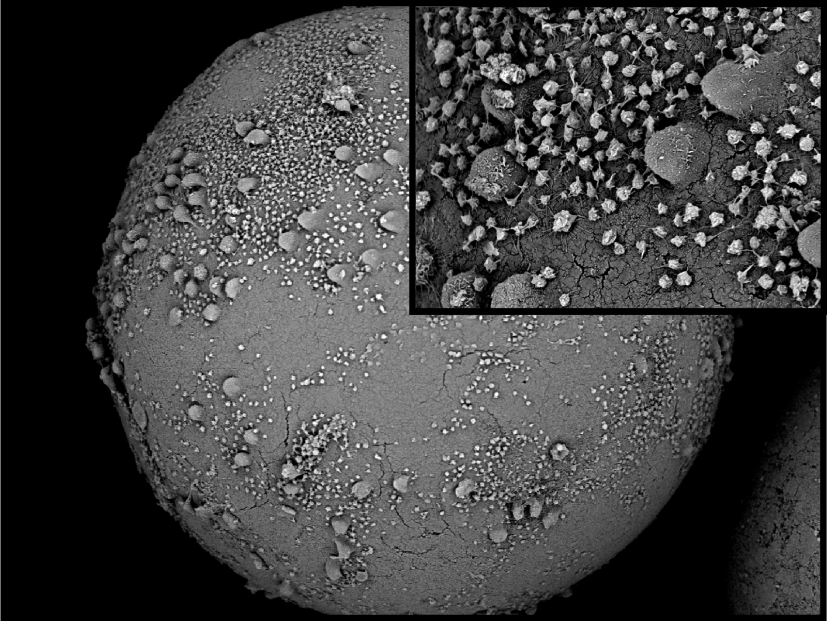

Extrakorporale Adsorptionsverfahren werden bei einer Reihe von Erkrankungen zur Unterstützung der Organfunktion bzw. zur Entfernung pathogener Substanzen aus dem Blut verwendet. Technisch können extrakorporale Adsorptionsverfahren entweder aus Plasma nach Abtrennung der Blutzellen oder direkt aus Vollblut durchgeführt werden. Vollblutaphereseverfahren sind technisch einfacher realisierbar als die Adsorption aus Plasma, erfordern jedoch besonders blutverträgliche Adsorberpolymere, um die Aktivierung und Adhäsion von Blutzellen an die Adsorberoberfläche während der Behandlung so gering wie möglich zu halten.

Auch bei klinisch etablierten Vollblutaphereseverfahren wird fallweise nach der Behandlung eine Thrombozytopenie, also eine starke Abnahme der Zahl der Blutplättchen, beobachtet, die eine weitere Verwendung des Verfahrens ausschließt. Die Mechanismen, die zur Plättchenaktivierung und zur Abnahme der Plättchenzahl führen, sind bisher ungeklärt.

Ziele des Projektes sind die Charakterisierung des Glykanmusters von Plättchen gesunder Spender, die Charakterisierung des Glykanmusters von Plättchen bei Infekten und die Untersuchung des Einflusses geänderter Glykanmuster auf die Bindung von Plättchen an Adsorberpolymere in extrakorporalen Kreisläufen.